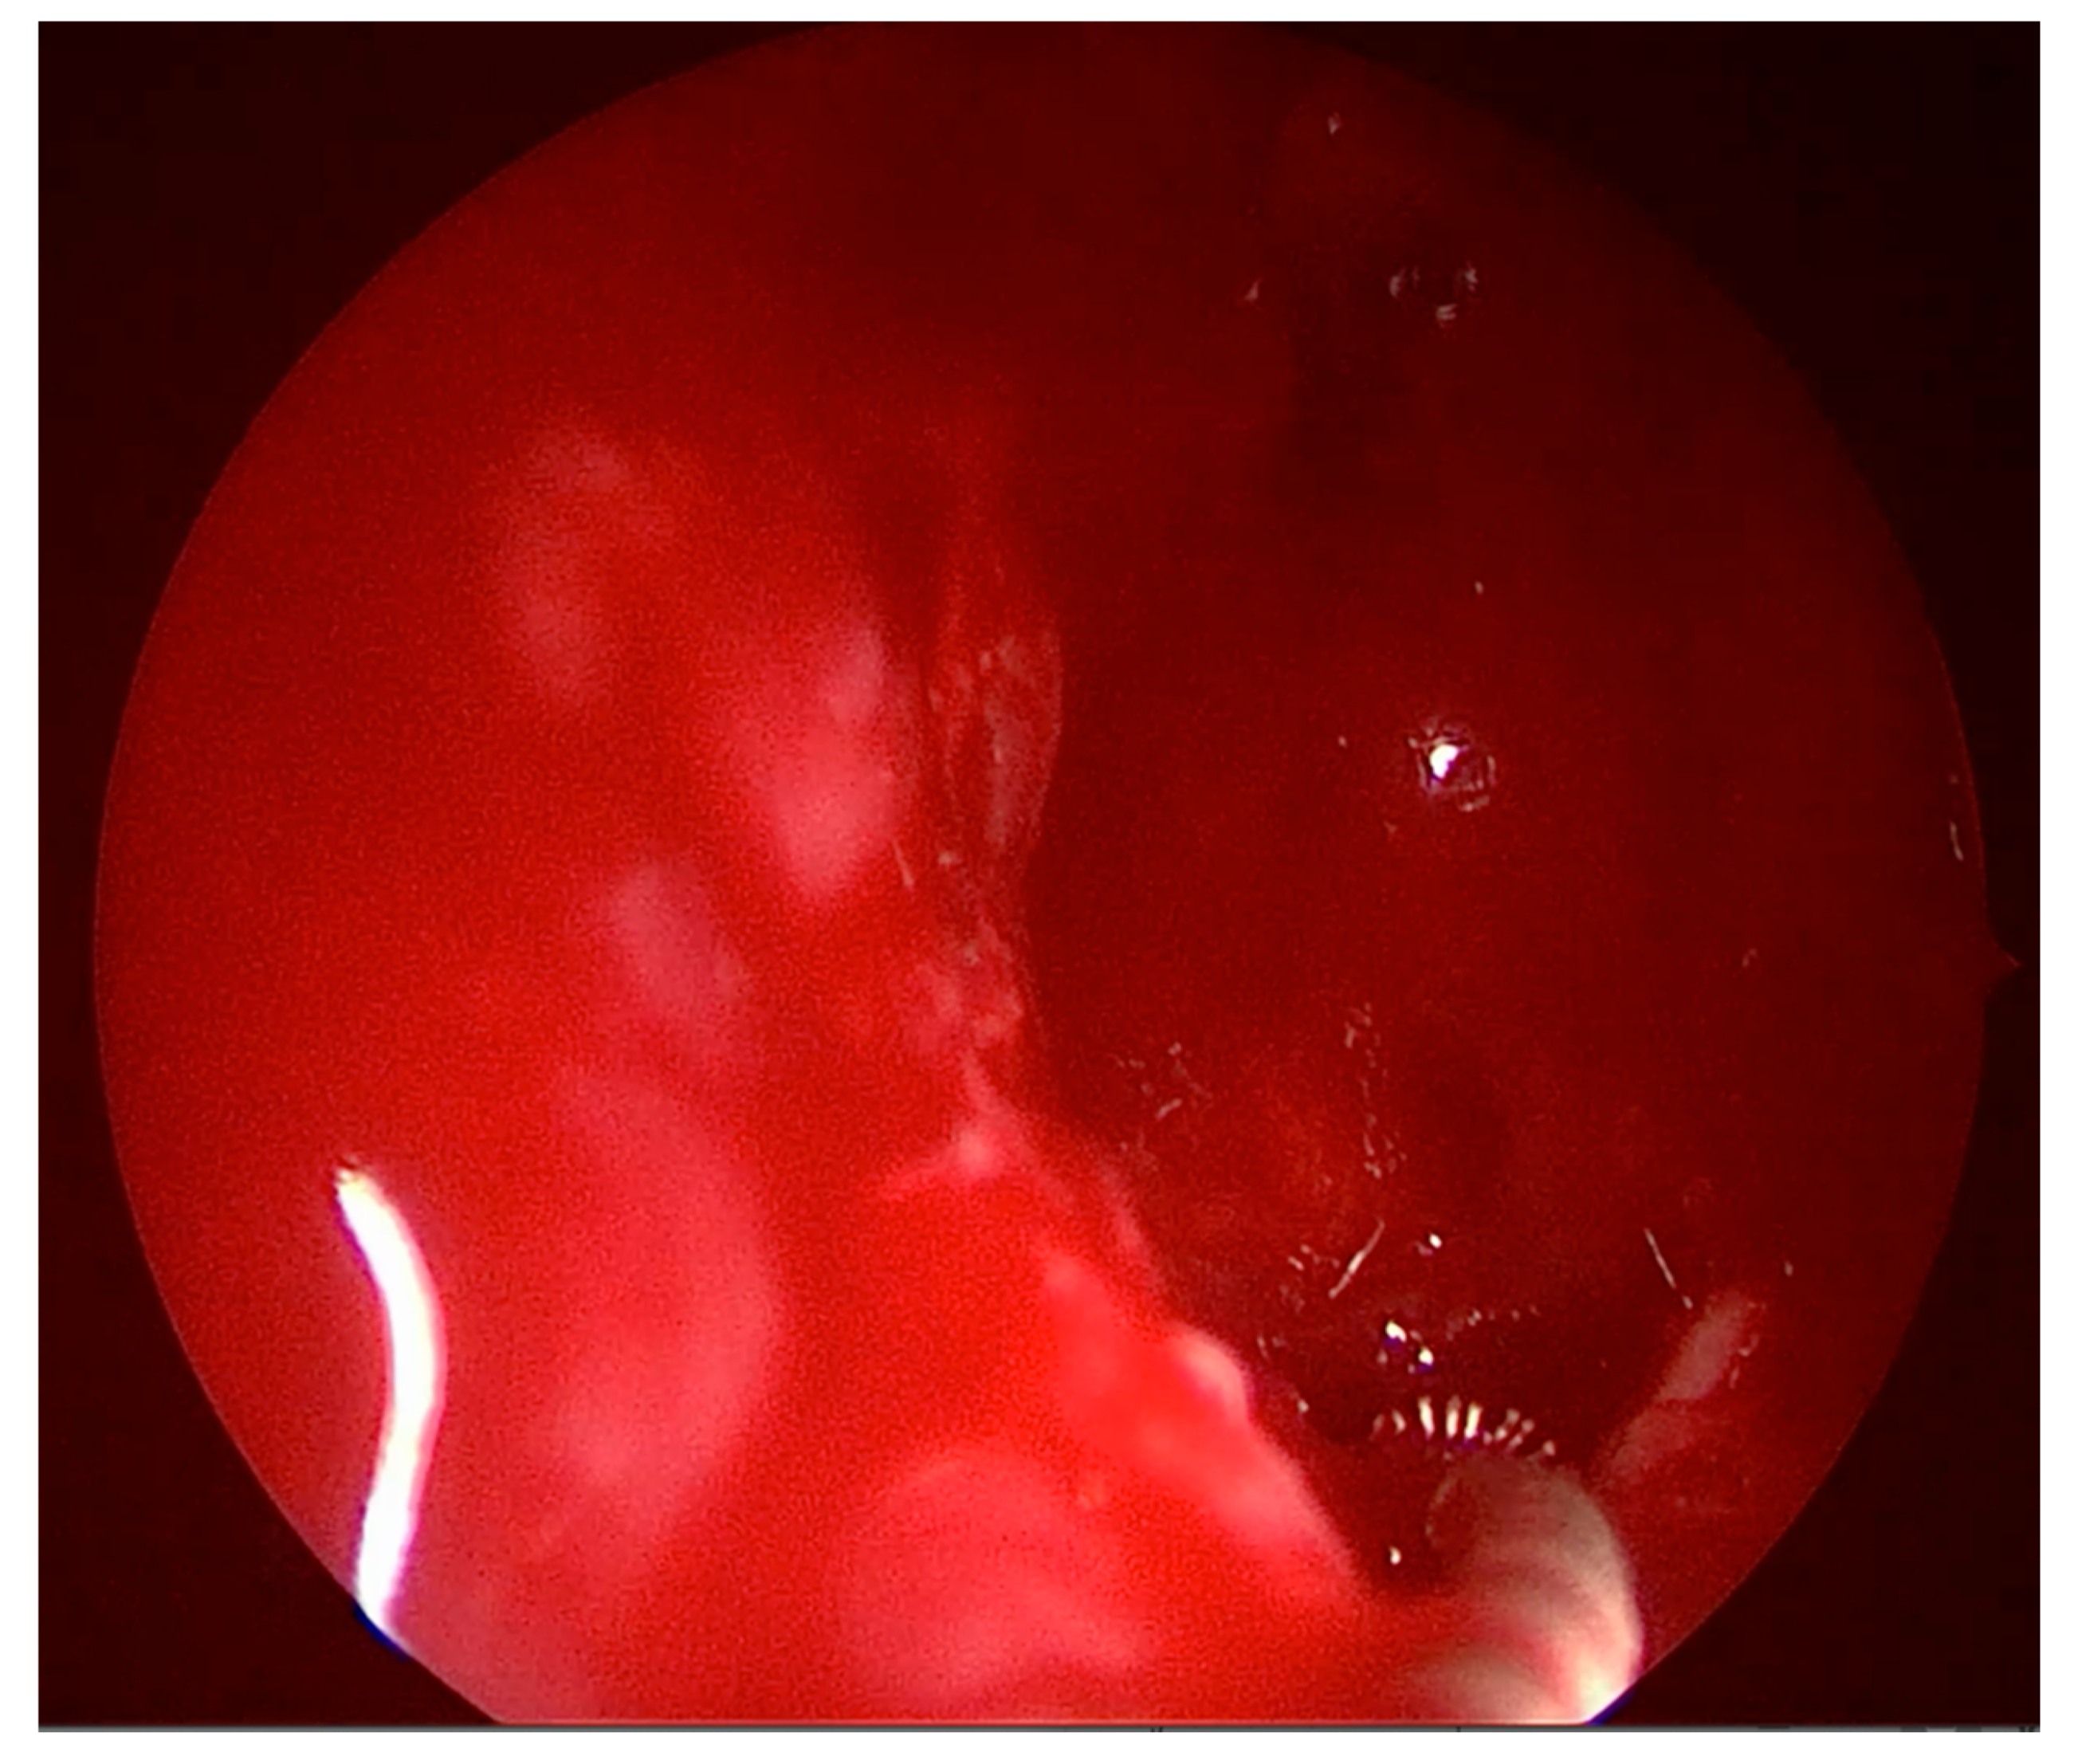

Figure 4.

The stylet being inserted under direct supervision into the lateral recess.